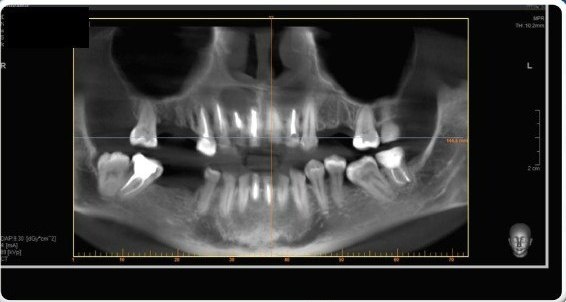

Жалобы были скромные — на периодические ноющие боли в области 11 зуба (центральный верхний зуб справа). Но при диагностике была выявлена серьезная проблема — трещина корня. Увы подобный диагноз не предполагает другого решения проблемы, кроме удаления. Также был диагностирован хронический периодонтит на 14 зубе (верхний правый сегмент зубного ряда, так же попадает в видимую зону при улыбке). Премоляр был ранее лечен по поводу периодонтита, но к сожалению консервативное лечение оказалось неэффективно. Ситуация также осложнялась тем, что ранее пациентке проводилось эндодонтическое лечение 11,12 зубов с последующей резекцией верхушек корней и удалением крупной радикулярной кисты, занимавшей почти весь объем костной ткани в области 11,12,13 зубов и до полости носа.

Сопоставление в специальной программе данных компьютерной томографии и цифрового скана зубов.